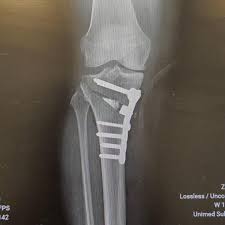

Filme De Raios X De Um Joelho De Um Paciente Com Tibia Proximal Fraturada Apos A Fixacao Da Placa E Dos Parafusos Foto Premium

Tibia Proximal Da Fratura Da Articulacao Do Joelho Do Raio X E De Reparo Do Cargo Tibia Proximal Da Fratura Imagem De Stock Imagem De Ferimento Ciencia 134286017

Raio X Articulacao Do Joelho Fratura Da Tibia Proximal E Fratura Pos Tibia Proximal Da Tibia Foto Premium